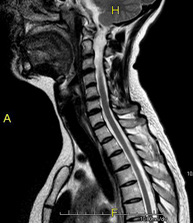

- RM Columna cervical

Prueba diagnóstica no invasiva que consiste en la obtención de imágenes de alta definición anatómica de la columna cervical mediante el empleo de un campo electromagnético y ondas de radio (con un emisor y un receptor). No utiliza radiación ionizante. Indicaciones: traumatismo, degeneración de la columna, hernias.